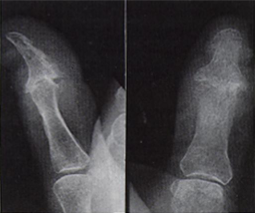

Radiograph: "Pencil in cup deformity"

Pencil in cup deformity

Psoriatic Arthritis